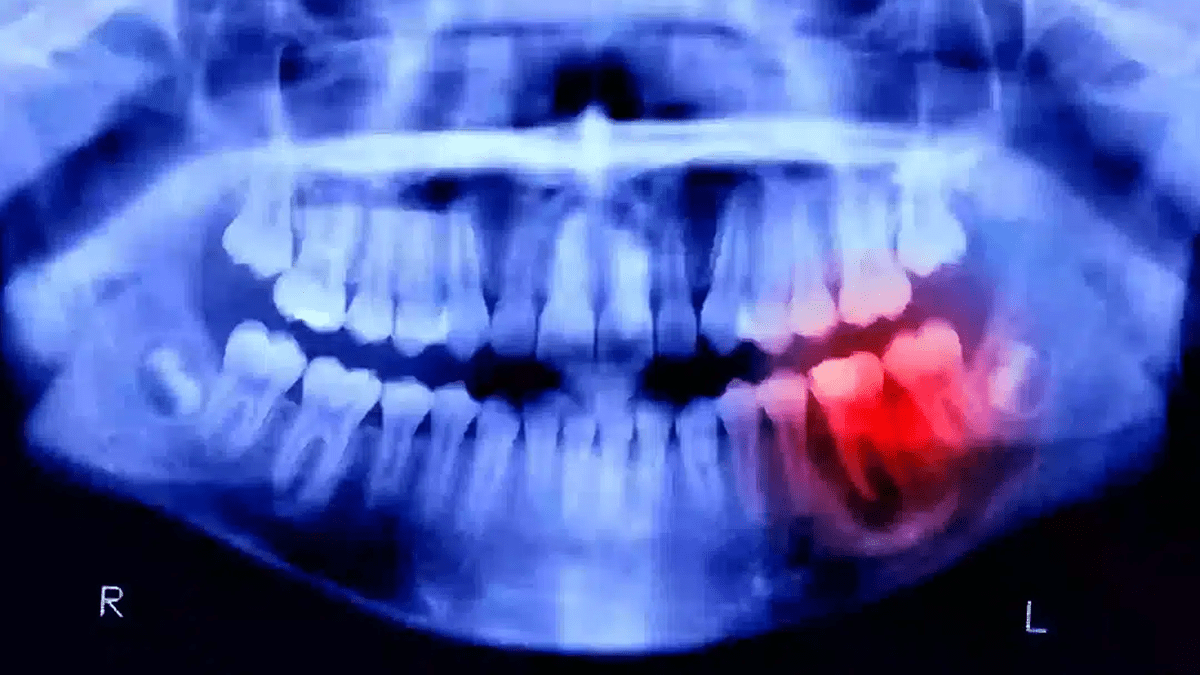

Estudos indicam que infecções bucais crônicas, como a periodontite, podem liberar bactérias e toxinas que chegam ao cérebro através da corrente sanguínea. Uma dessas bactérias, chamada Porphyromonas gingivalis, comum em casos de gengivite e periodontite, foi encontrada em amostras cerebrais de pacientes com Alzheimer.

Essas substâncias podem provocar inflamações no tecido cerebral e contribuir para a formação de placas beta-amiloides — um dos principais marcadores da doença.

- Infecções bucais crônicas, como a periodontite, liberam bactérias e toxinas que podem atingir o cérebro pela corrente sanguínea.

- A bactéria Porphyromonas gingivalis, comum em casos de gengivite, foi identificada em amostras cerebrais de pacientes com Alzheimer.

- Essas bactérias produzem enzimas chamadas gingipaínas, que provocam inflamações e danos às células cerebrais.

- A inflamação crônica causada por essas infecções pode acelerar o processo de degeneração neural.